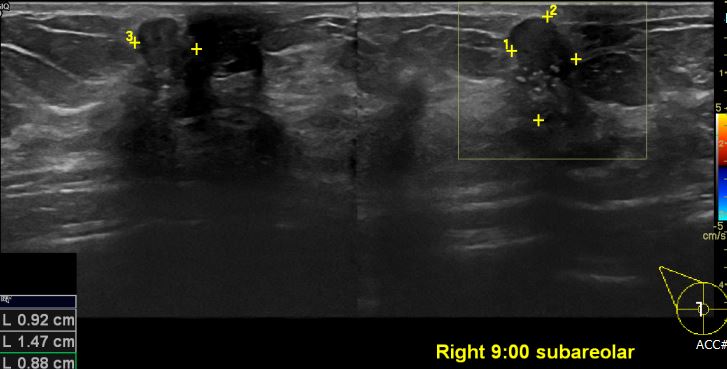

상기환자 유측 유방에 만져지는 멍울로 내원하신 50대 여성분으로 우측 9시 방향 유두

밑 조직검사 시행하여 우측 침윤성 유관암 진단 되었습니다.